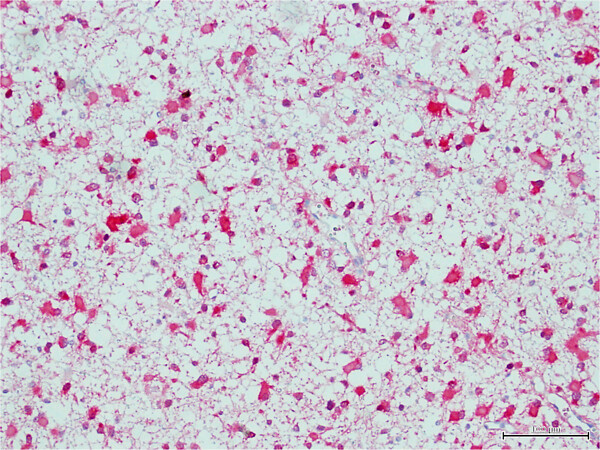

OKImmunohistokemia